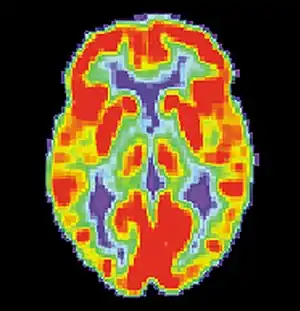

Brain positron emission tomography is a form of positron emission tomography (PET) that is used to measure brain metabolism and the distribution of exogenous radiolabeled chemical agents throughout the brain. PET measures emissions from radioactively labeled metabolically active chemicals that have been injected into the bloodstream. The emission data from brain PET are computer-processed to produce multi-dimensional images of the distribution of the chemicals throughout the brain.[1]: 57

The positron emitting radioisotopes used are usually produced by a cyclotron, and chemicals are labeled with these radioactive atoms. The radioisotopes used in clinics are normally 18F (fluoride), 11C (carbon) and 15O (oxygen). The labeled compound, called a radiotracer or radioligand, is injected into the bloodstream and eventually makes its way to the brain through blood circulation. Detectors in the PET scanner detect the radioactivity as the compound charges in various regions of the brain. A computer uses the data gathered by the detectors to create multi-dimensional (normally 3-dimensional volumetric or 4-dimensional time-varying) images that show the distribution of the radiotracer in the brain following the time. Especially useful are a wide array of ligands used to map different aspects of neurotransmitter activity, with by far the most commonly used PET tracer being a labeled form of glucose, such as fluorodeoxyglucose (18F).[2]

The greatest benefit of PET scanning is that different compounds can show flow and oxygen, and glucose metabolism in the tissues of the working brain. These measurements reflect the amount of brain activity in the various regions of the brain and allow to learn more about how the brain works. PET scans were superior to all other metabolic imaging methods in terms of resolution and speed of completion (as little as 30 seconds), when they first became available. The improved resolution permitted better study to be made as to the area of the brain activated by a particular task. The biggest drawback of PET scanning is that because the radioactivity decays rapidly, it is limited to monitoring short tasks.[1]: 60 >